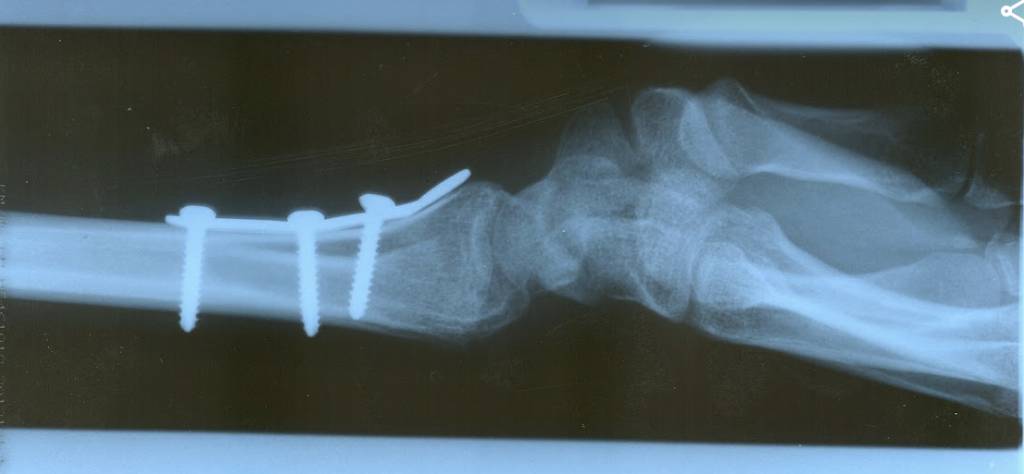

I've had a little fall and broken my radius, oops. The initial break was 30/05 and it was plated on 06/06, wound check and new cast on Friday. I'm pretty sure there will be a few people here that have done similar so please share recovery dos and don'ts.

Pics for context

I’ve had this* (although I was 18 at the time so healed quickly) after coming off my bike and landing on an outstretched hand. It didn’t reduce under traction and was plated the next day. Backslab for 48 hours then a half-length cast which left thumb and fingers free to move. Wasn’t the neatest operation in the world because the screws are about 5mm too long and stick out the other side.

Surgeon said that it needed four weeks post-op. I was carrying shopping bags after two, and lied to a different hospital 21 days later and had the cast removed after an x-ray. The consultant there said that he didn’t use a cast at all and it’s down to personal preference. I worked on the principle that if it didn’t hurt it was probably OK.